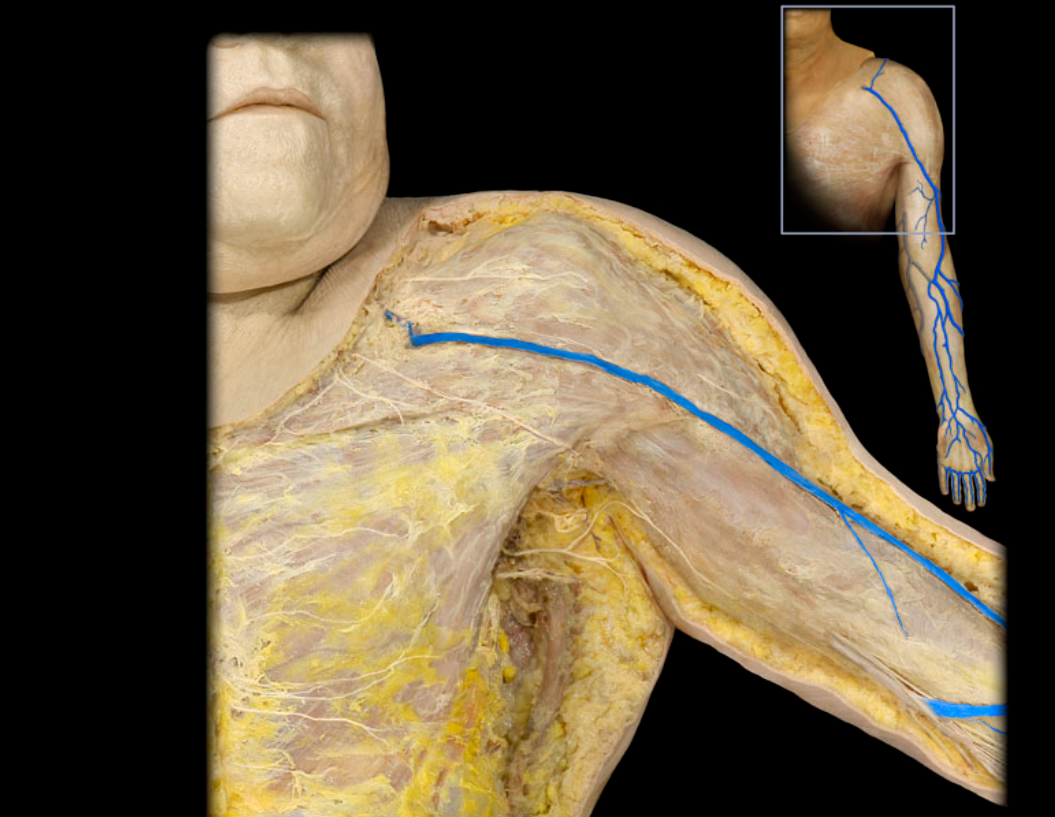

Basilic v.

Cephalic v.

Cephalic v. and tributaries

Median cubital v.

Subclavian v.